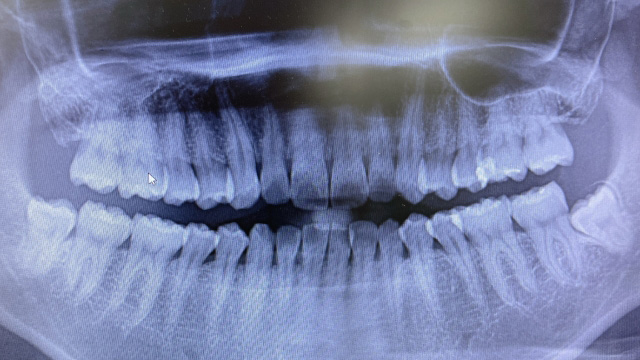

最新のレントゲン撮影機を導入しておりますので、より精密な検査ができ、むし歯の部分だけを正確に削り取ることができるのです。